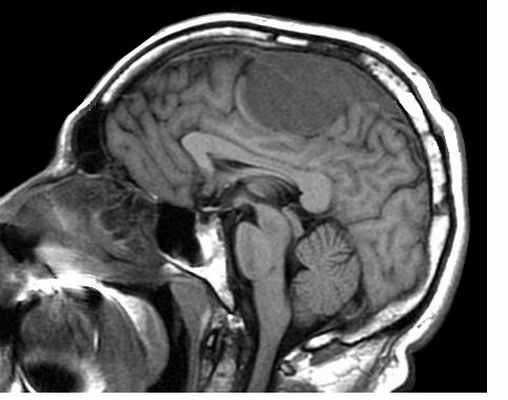

МРТ головного мозга. Менингиома верхнего сагиттального синуса. Аксиальная Т2-взвешенная МРТ и сагиттальная Т1-взвешенная МРТ и сагиттальная МР-венограмма.

МРТ головного мозга. Субфронтальная менингиома. Сагиттальная Т2-взвешенная МРТ.